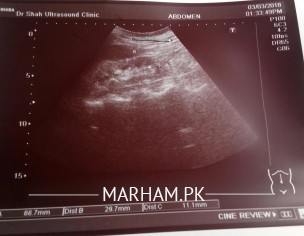

Doctors especially nephrologist . please see this ultrasound are the kidneys?about size and shape?(Rt.78x26.2x9.5mm).(left.66.7x29.7x11.1mm) size is in some one tell me?

Kidneys are relativly smaller and echogenic

Is ur mothers serum creatinine normal?

Thanks For response,my mom have kidney dieseas. Is this really small,i mean serious.?What Is normal size in mm?